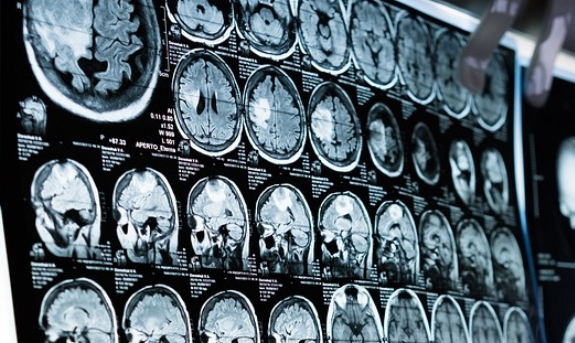

해마(Hippocampus)는 뇌의 일부분으로 장기적인 기억과 공간개념, 감정적인 행동을 조절하는 역할을 한다. 기억과 학습을 관장하는데, 단기기억이나 감정이 아닌 서술기억을 처리하는 장소로 주로 좌측 해마는 최근의 일을 기억하고, 우측 해마는 태어난 이후의 모든 일을 기억하며, 새로운 사실을 학습하는데, 해마가 손상되면 새로운 정보를 기억할 수 없게 된다. 보스턴 하버드 의과대학의 Bernard Hanseeuw 박사가 연구팀은 평균 72세 128명으로부터 수집한 뇌 스캔 데이터에 초점을 맞췄다. 스캔을 사용하여 아밀로이드 플라크 또는 타우 엉킴의 뇌 수준 변화를 추적했다. 둘 다 알츠하이머병 발병과 관련이 있다. 또한 연구팀은 매년 촬영한 스캔을 사용하여 7년 동안 개인의 해마 크기 변화를 차트로 표시했다. 그 결과 연구팀은 해마에서 가장 심각한 수축을 보인 사람들은 연구 기간 동안 사고력 저하를 보일 가능성도 가장 높았다고 보고했다. Hanseeuw 박사는 “이는 아밀로이드나 타우 수준의 변화와는 독립적으로 발생하는 것으로 보인다. 그들은 해마 수축이 사고 저하의 10%를 차지할 수 있다.”고 추정했다. Hanseeuw 박사는 미국 신경학회(American Academy of Neurology)의 보도 자료에서 “이러한 결과는 알츠하이머병 이외의 신경퇴행성 질환이 이러한 감소에 기여하고 있음을 시사하며, 해마 부피를 측정하면 현재 측정하기 어려운 이러한 원인을 평가하는 데 도움이 될 수 있다.”라고 밝혔다. Hanseeuw 박사는 “이번 연구는 이러한 신약에 누가 반응할지, 그리고 사람들의 인지 저하 궤적을 더 잘 예측하는 데 도움이 될 수 있을 것”이라고 덧붙였다. 이번 연구 결과는 최근 Neurology 저널에 게재되었다.